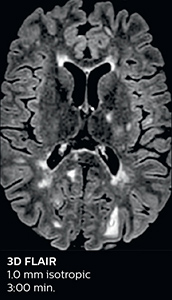

The abbreviated MS protocol for brain is only around 9 minutes, so in case of suspected multiple sclerosis, one or two more advanced sequences may be added, such as PSIR (phase sensitive inversion recovery) or susceptibility-weighted sequences to help us make more confident diagnoses in these inflammatory cases.

In this example, the optional 3D multishot susceptibility weighted sequence with 0.6 mm isotropic voxels is 2 lesions with a central vein sign (arrows) and one lesion with a phase-rim sign (arrowhead). The total scan time, including SmartBrain and axial PD/T2 3mm, is 11:10 min. and is 18:30 min. with the optional 3D PSIR and 3D SWI multishot included.

“We used to have long examination times for certain types of patients, a few lasting more than 40 minutes,” says Dr. Savatovsky. “What is remarkable, is that now all these examinations are below 30 minutes, which opens up opportunity to add more sequences when needed. It’s really hard to keep a patient for more than 40 minutes in the scanner, but because we have now cut scan times by at least 10 minutes, we can add more sequences without making the exam too long. And this is where the new system helps us make a difference. Examples include our examinations for informing brain tumor classification or giant cell arteritis workup, or for intracranial wall imaging – so in patients where we need several advanced sequences or high resolution sequences.” “We added three additional sequences in our brain neoplasm classification exam: a 3D SWI sequence, APT and ASL on top of 3D morphologic sequences, an isotropic DSC (dynamic susceptibility contrast) and multivoxel spectroscopy. I think that in patients that need a classification for brain mass, for example, we can provide a more detailed and confident diagnosis than before, allowing the clinicians to decide for either a medical workup if no tumor is suspected, or for neurosurgery as soon as possible if a neoplasm is suspected.” “In multiple sclerosis patients, we increasingly include a multishot susceptibility sequence [3] in our routine cases, thanks to the shorter scan times. Our abbreviated MS protocol for brain is around 8 to 9 minutes, so we can ask for one or two additional sequences to visualize the central veins, or to get an additional contrast to better depict posterior fossa lesions. In cases of white matter lesions of unknown significance on FLAIR images, for example when we see high signal hyperintensities in the brain, we can add on more advanced sequences such as PSIR (phase sensitive inversion recovery) or susceptibility-weighted sequences to help us in distinguishing between MS and nonspecific or vascular abnormalities in these inflammatory cases.”